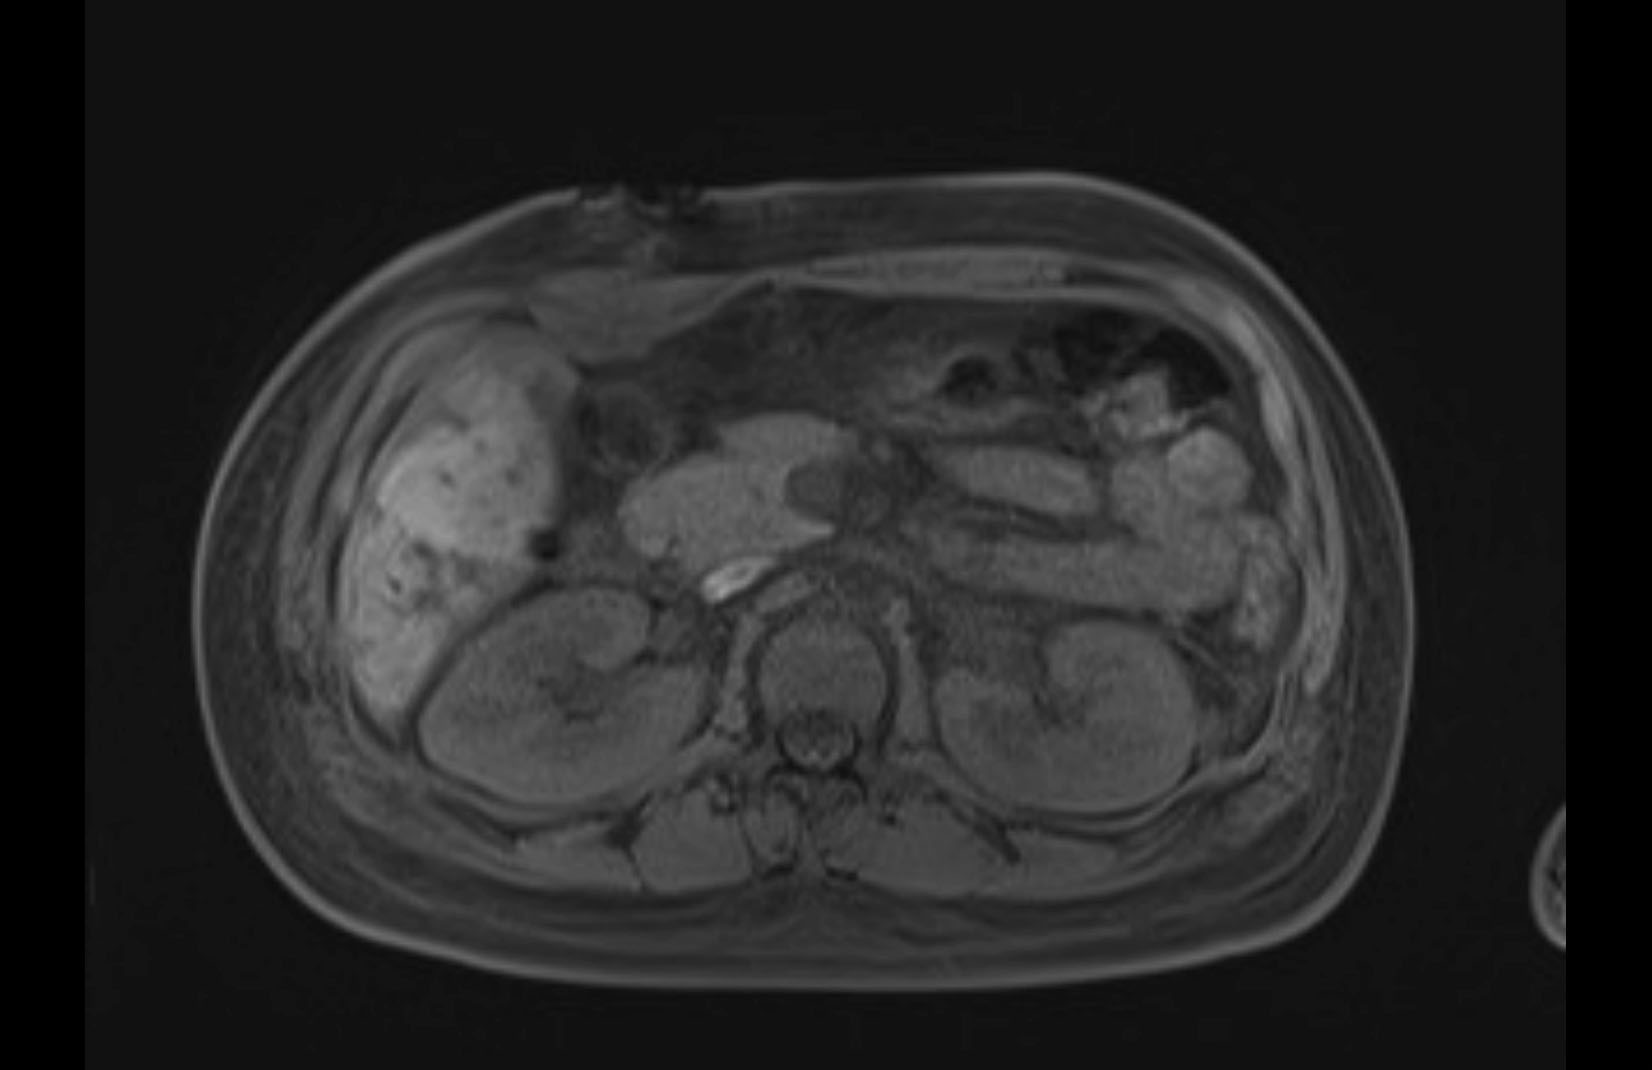

Imaging Analysis

Look through the patient's CT scan to identify any areas of concern for the necessary procedure.

MRI T1

MRI T2

Based on initial findings, which issue(s) would you be most concerned about?